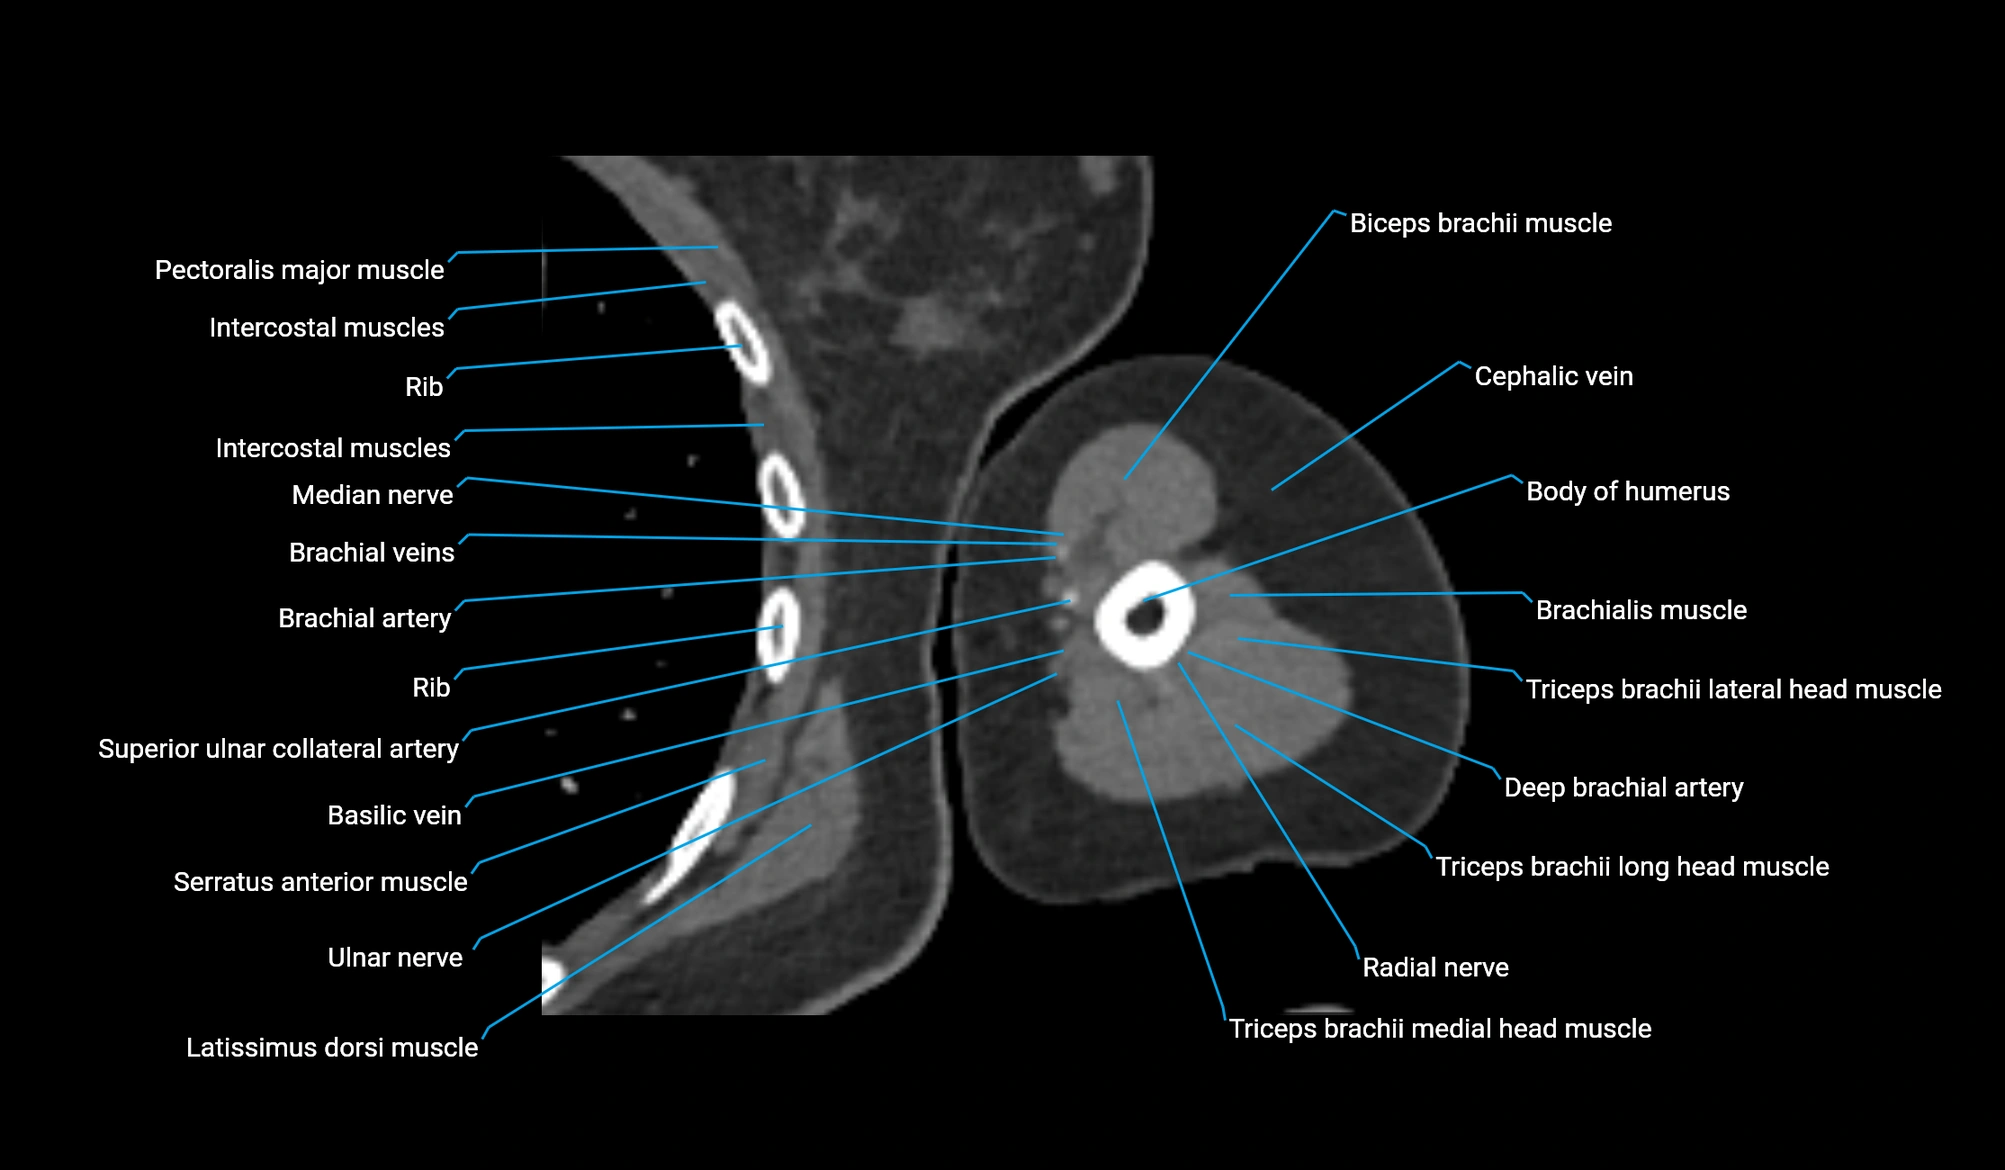

- Body of humerus

- Brachial artery

- Brachialis muscle

- Cephalic vein

- Lateral head of triceps brachii muscle

- Long head of triceps brachii muscle

- Medial head of triceps brachii muscle

- Median nerve

- Pectoralis major muscle

- Radial nerve

- Superior ulnar collateral artery

- Triceps brachii muscle